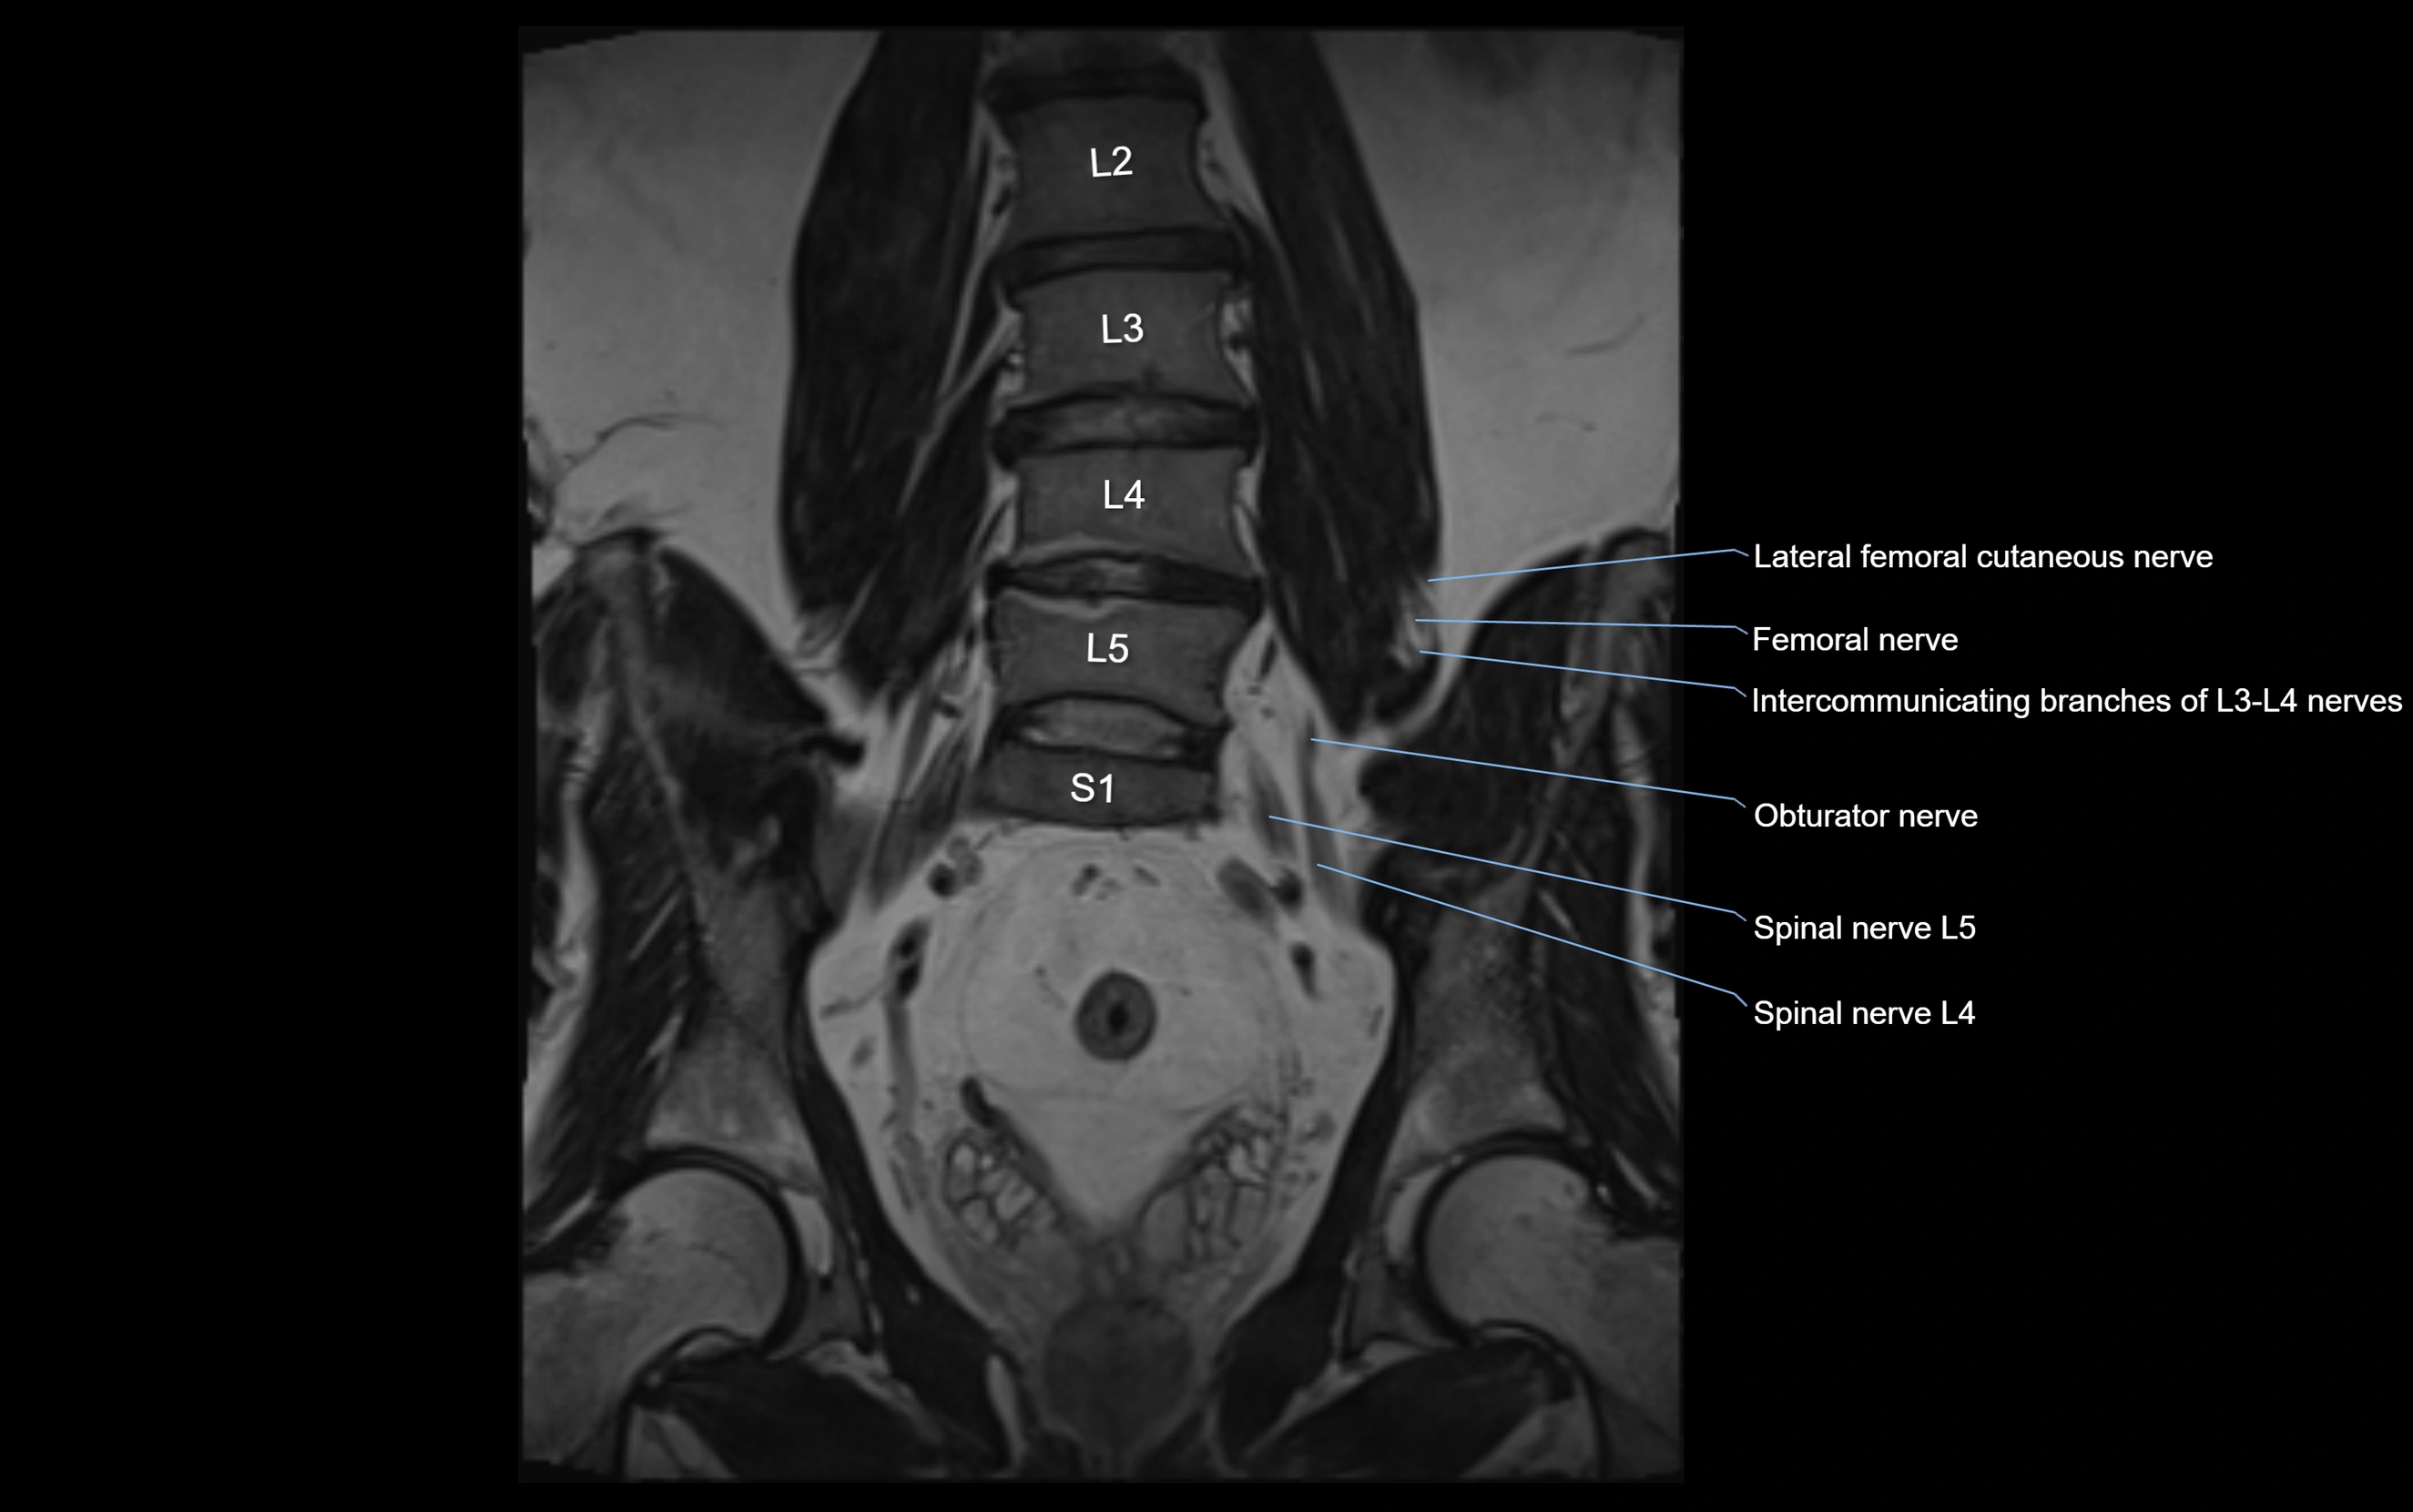

MRI Appearance

T1-weighted images:

• Nerve appears as a very thin low-to-intermediate signal intensity structure

• Surrounded by bright fat, aiding visualization

T2-weighted images:

• Nerve shows intermediate to mildly hyperintense signal compared to muscle

• Pathological involvement appears brighter

STIR (Short Tau Inversion Recovery):

• Normal nerve appears dark

• Inflamed or entrapped nerve appears bright hyperintense

T1 Fat-Sat Post-Contrast:

• Normal nerve enhances minimally

• Pathologic nerve (neuritis, entrapment, tumor infiltration) shows focal or diffuse enhancement

3D T2 SPACE / CISS:

• Nerve appears intermediate to mildly hyperintense compared to muscle

• Surrounded by bright fat or CSF, improving visualization

• Best sequence for mapping small pelvic nerves such as the anococcygeal